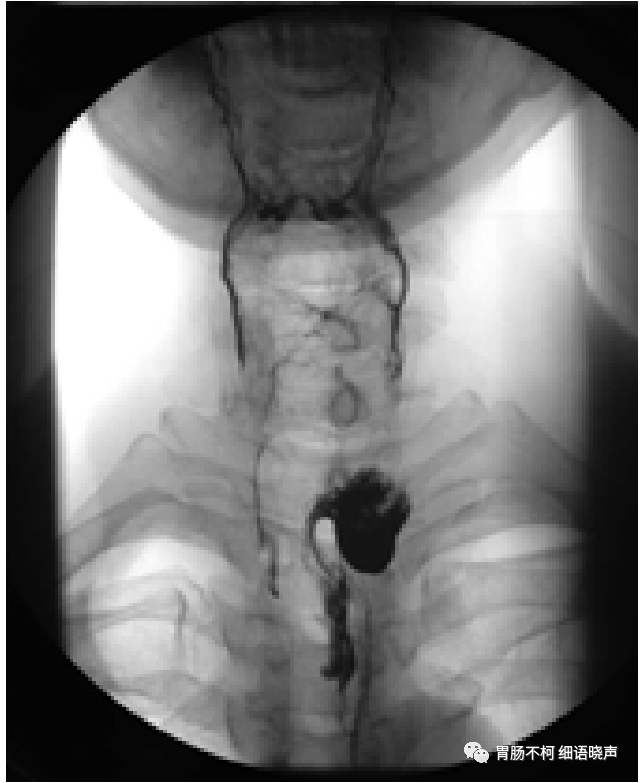

病例二:甲状腺左叶后方强回声型咽食管Killian-Jamieson憩室(此病例由杭州市第一人民医院韩志江主任提供)。

食道左侧壁见一囊袋状突起,边缘光滑。